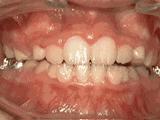

第一种

前牙移位,因为有牙齿缺失,导致相邻牙齿开始没有秩序的前突,经过矫正后是这样的~